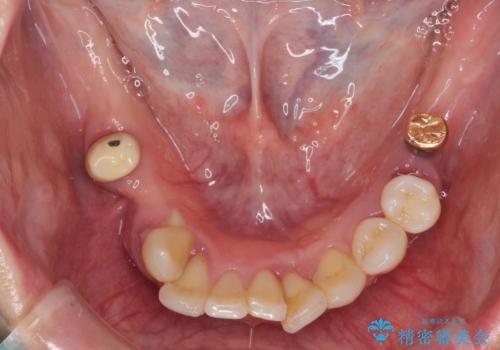

- 歯周病を放置したことで奥歯が抜け、前歯も痛くなってきたとのことで来院された患者様です。

奥歯はほとんどを抜歯しなければならない状態であり、抜歯をせずに済む歯も歯周外科処置や矯正治療を行う必要がある状態でした。

歯を抜かないといけない部分はインプラントとオールセラミッククラウンにより咬合を回復させ、歯周外科処置を行う歯については、同じくオールセラミッククラウンにて補綴治療を行うこととしました。